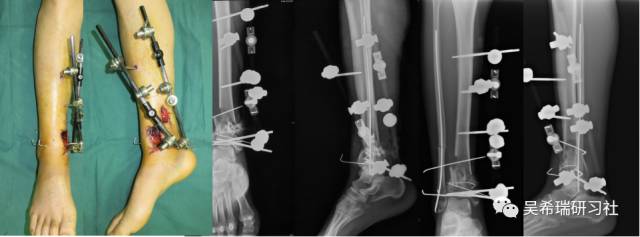

双下肢车祸外伤保肢的理由是足底皮肤好

TIPS:清创&盐水冲洗(不用双氧水)VSD骨水泥技术&开放植骨单边外固定架(下胫腓联合固定)早期下地 生理应力 + 机械应力游离植皮 / 不用皮瓣清创时游离皮质骨去除胫跖骨牵引技术防治&纠正足下垂